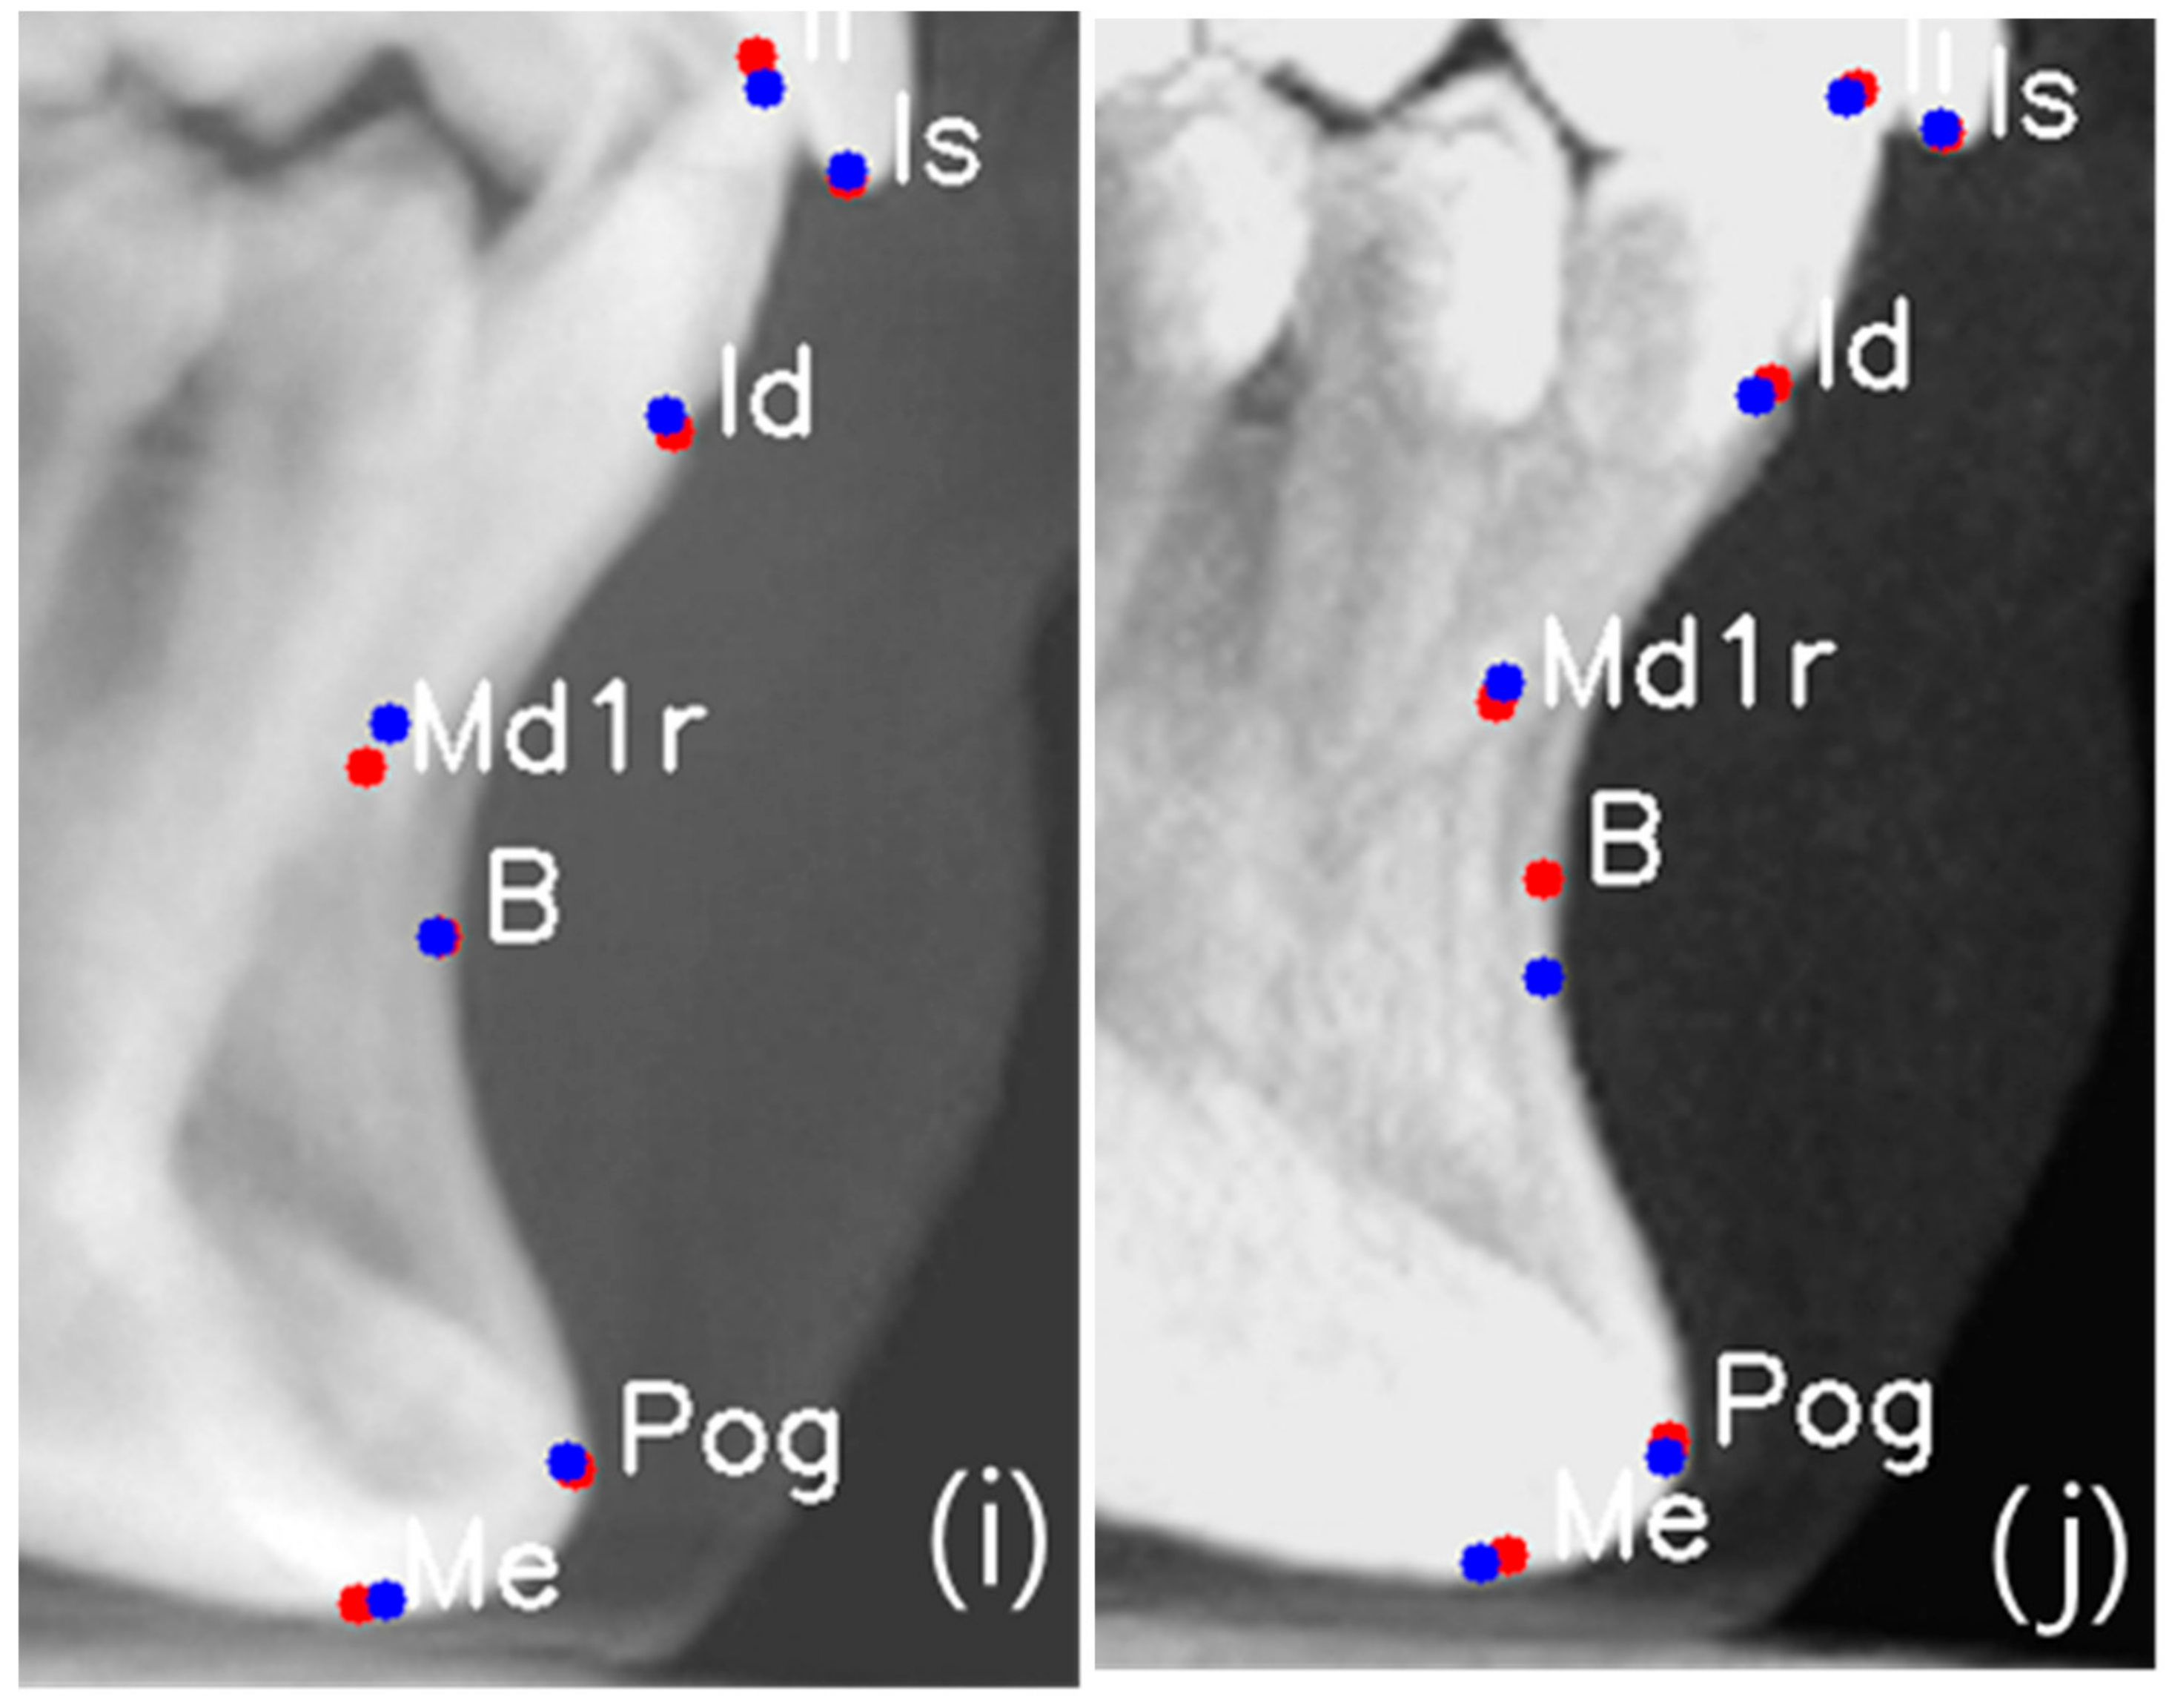

Figure 5.

Comparison of AI prediction between CBCT-LC (a,c,e,g,i) and MIP-LC (b,d,f,h,j); Orbitale c and d; Maxilla e and f; Porion g and h; and Mandible i and j. The red dot is manual identification (truth ground), and the blue dot is AI prediction.